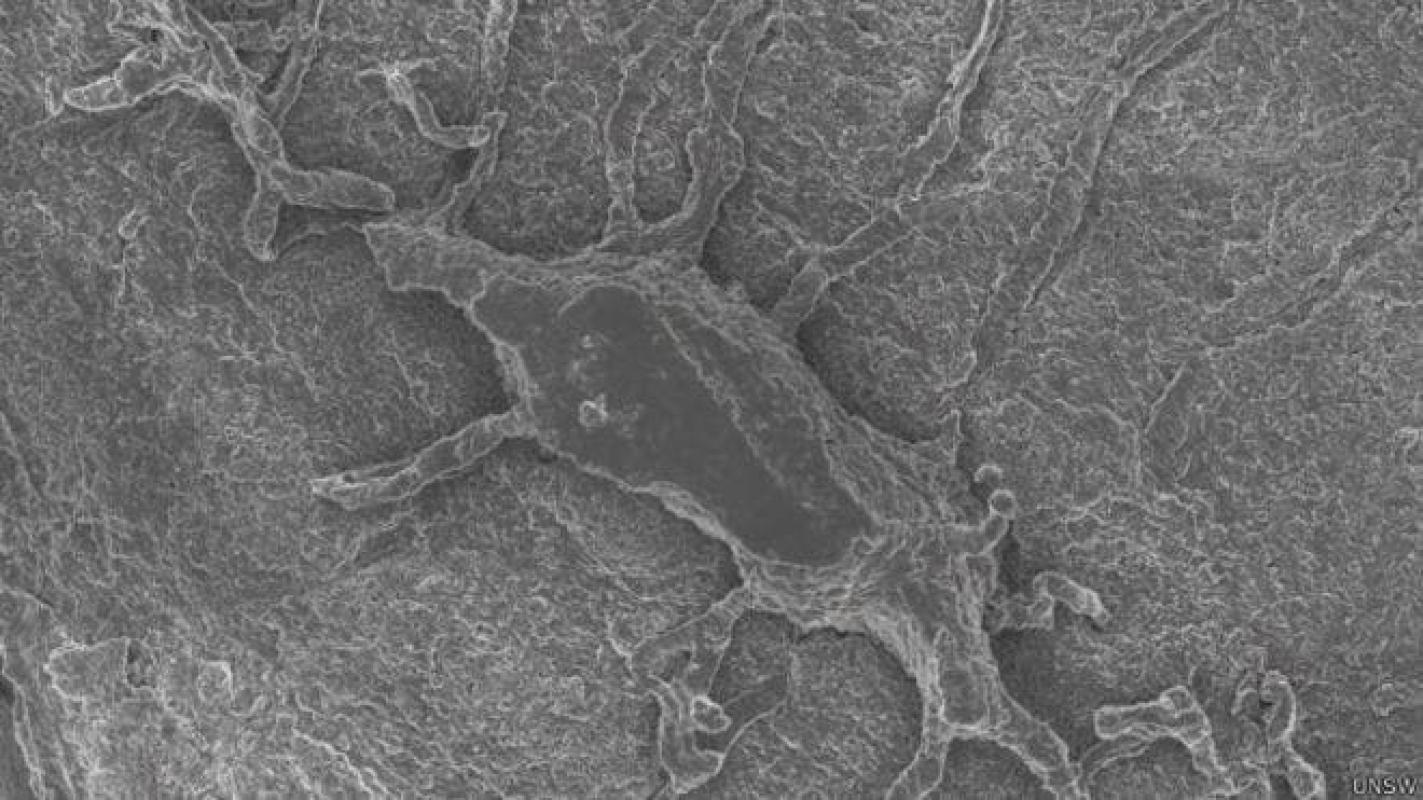

Para conseguirlo, lo primero era tener las imágenes de los distintos niveles del cuerpo.

Con ese objetivo, la profesora y su universidad forjaron una alianza con el fabricante alemán de instrumentos de medición óptica Zeiss, que proporcionó la tecnología para tomar estas imágenes del organismo a distintos niveles.

Por el momento ya han conseguido mostrar cómo funcionaría en el interior de una rodilla.